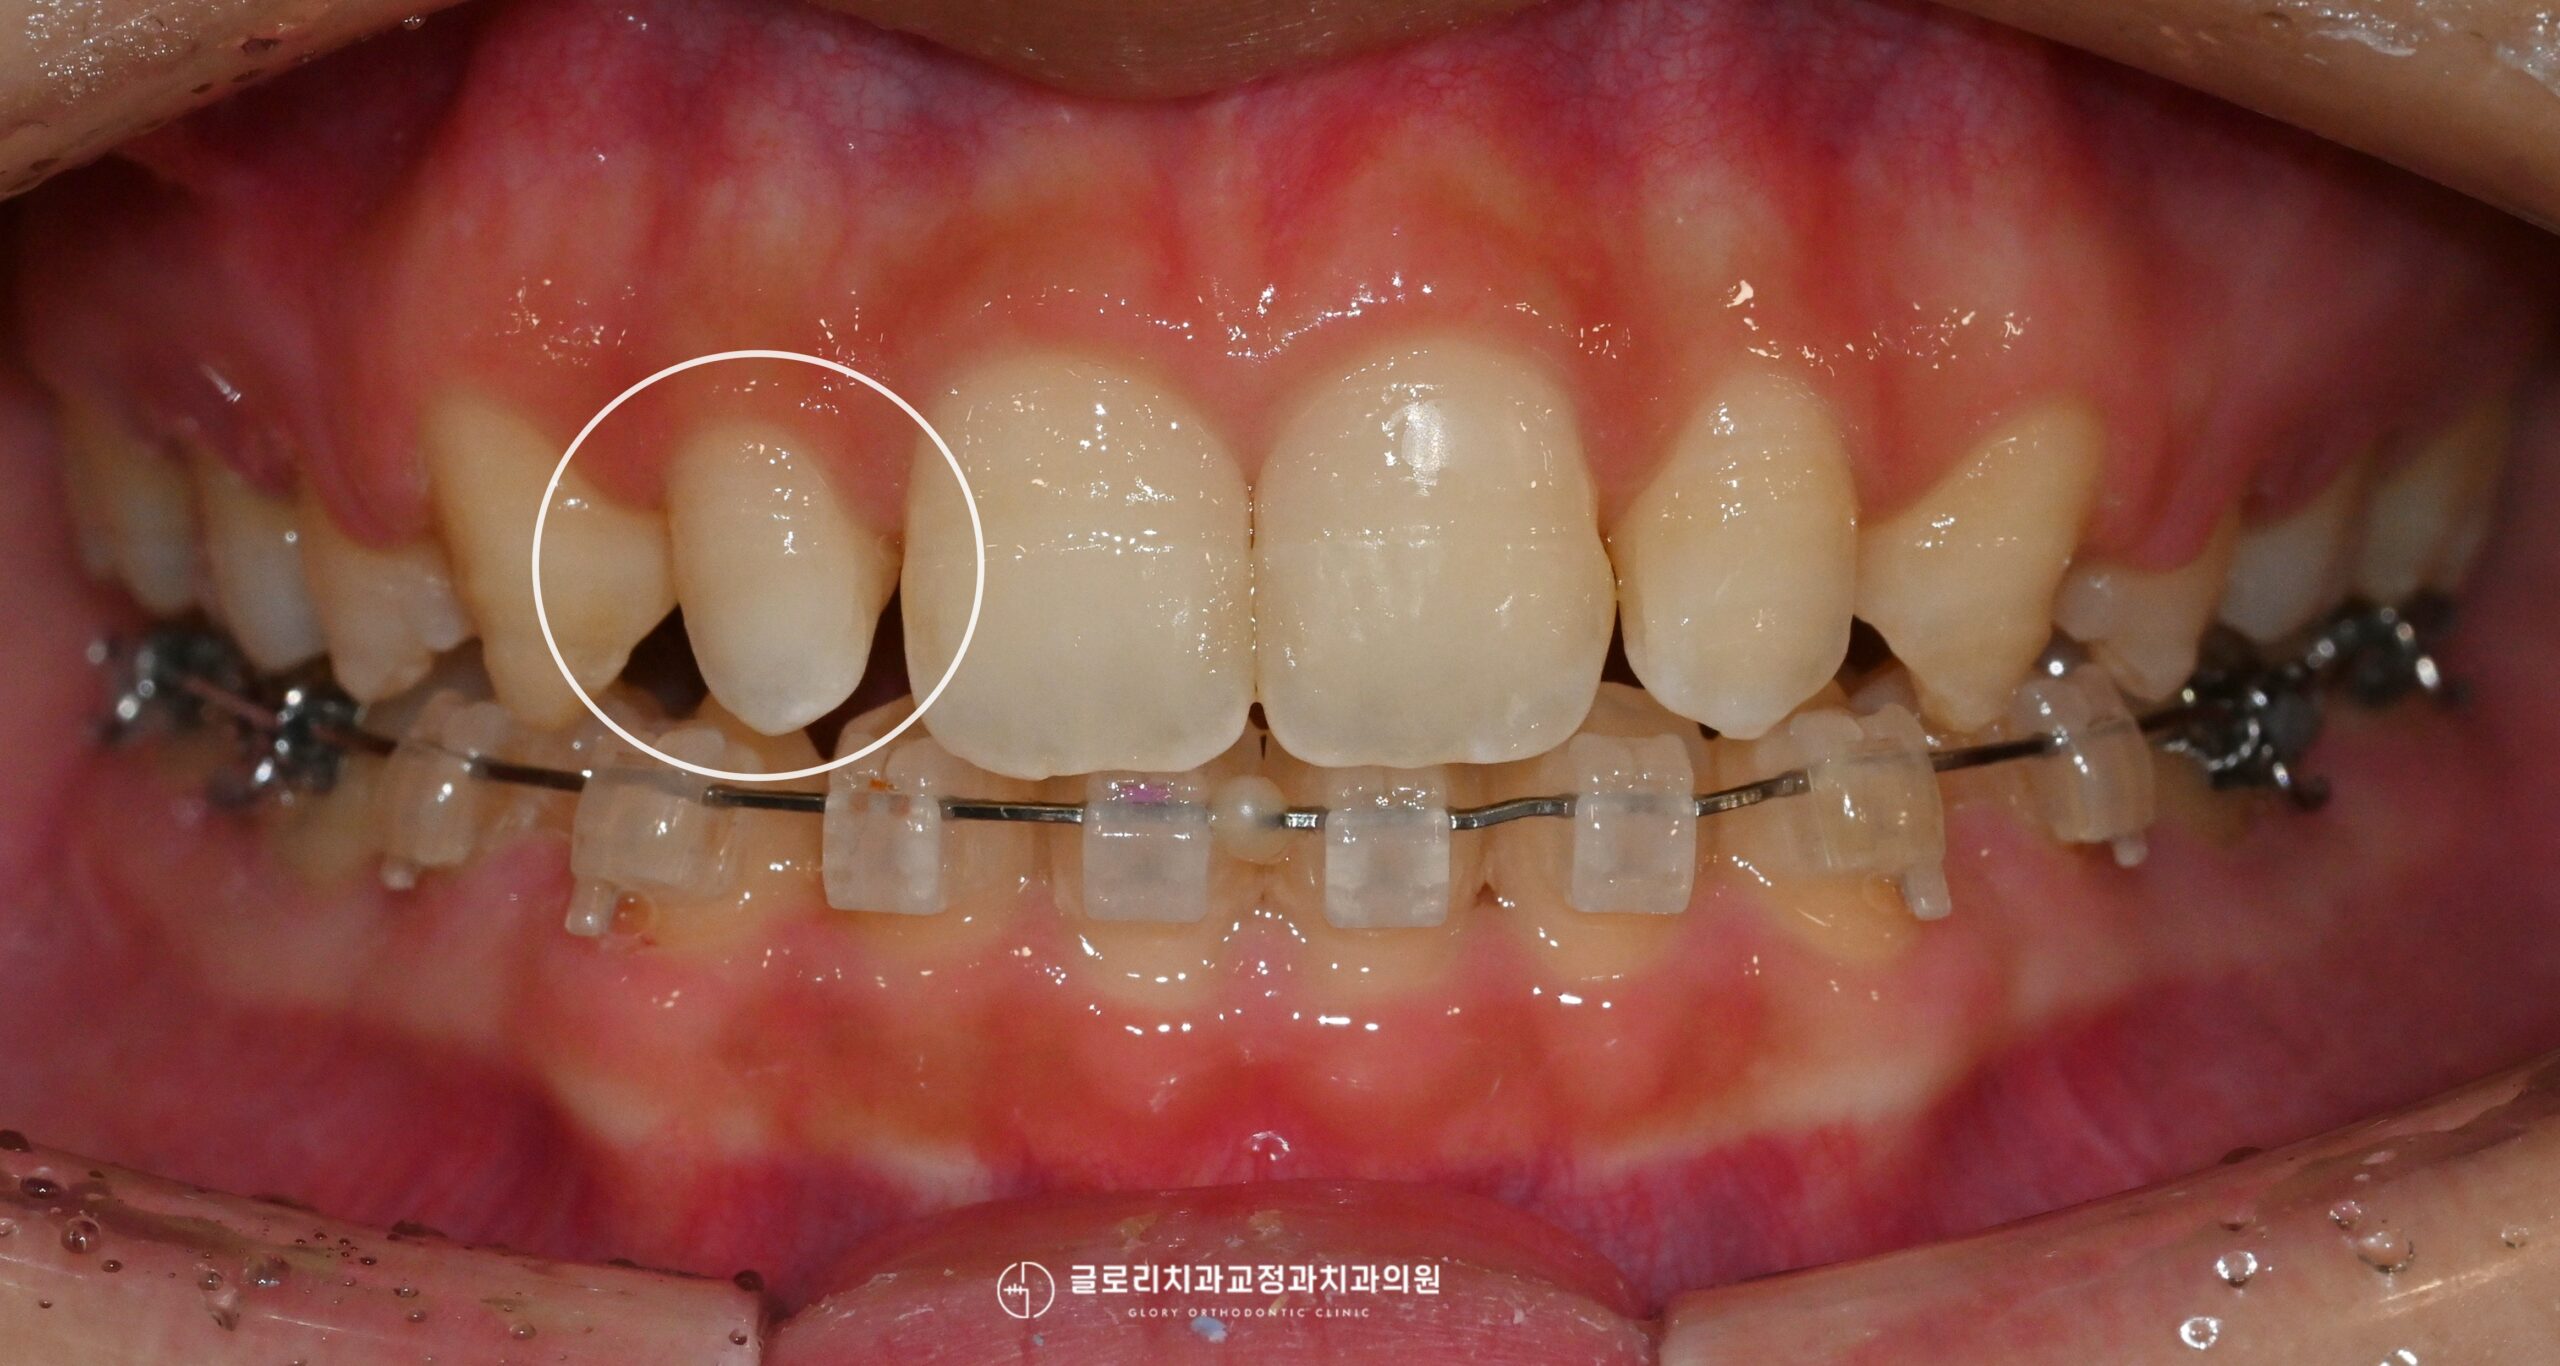

상봉역 교정치과 에서 보여드리는 사진과 같이 치아를 뺀뒤 치면에 브라켓과 와이어를 부착, 고무줄을 이용해 치아를 움직이게 됩니다.

초기에는 비교적 얇고 유연한 와이어를 사용하여 배열을 부드럽게 정렬하는 단계가 진행되는데 이 과정에서는 뒤틀림을 바로잡고, 이가 이동할 수 있는 기본 환경을 만들어주는 것이 목적이라 할 수 있습니다.

상봉역 교정치과 에서 보여드리는 사진을 보면 현재 발치교정을 통해 대부분의 공간이 닫히고 배열이 가지런해진 것을 알 수 있습니다.

이제 미세한 조정을 통해 교합의 정밀함을 맞추는 과정이 필요한데 현재 상악의 경우 왜소치 치료가 필요할 것으로 보입니다.

왜소치의 치료방법은 여러가지가 있는데 이번 케이스의 경우 자연치 보존을 우선으로 고려한 라미네이트를 계획합니다.